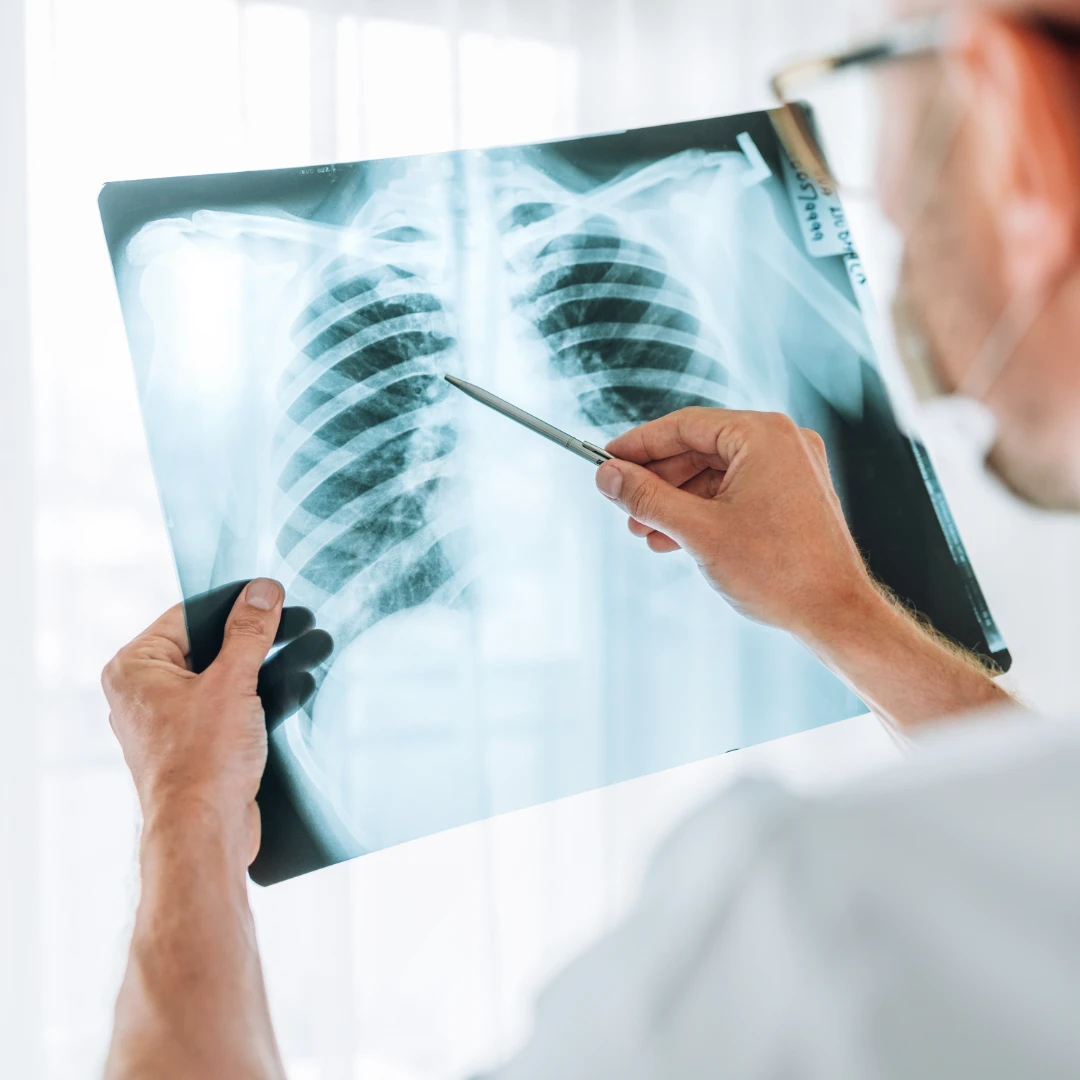

Chest X-ray: useful in evaluating lung abnormalities such as infection and tumour. The surrounding structures, such as the silhouette of the heart and the anatomy of the ribs, can also be seen in a chest X-ray.